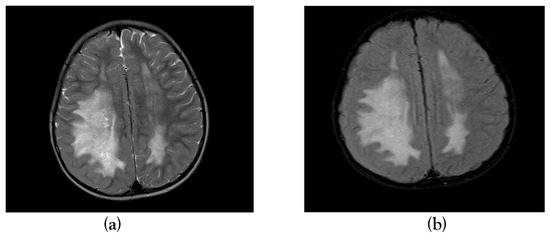

A Case Report of Acute Disseminated Encephalomyelitis Following Severe Dengue in a Child